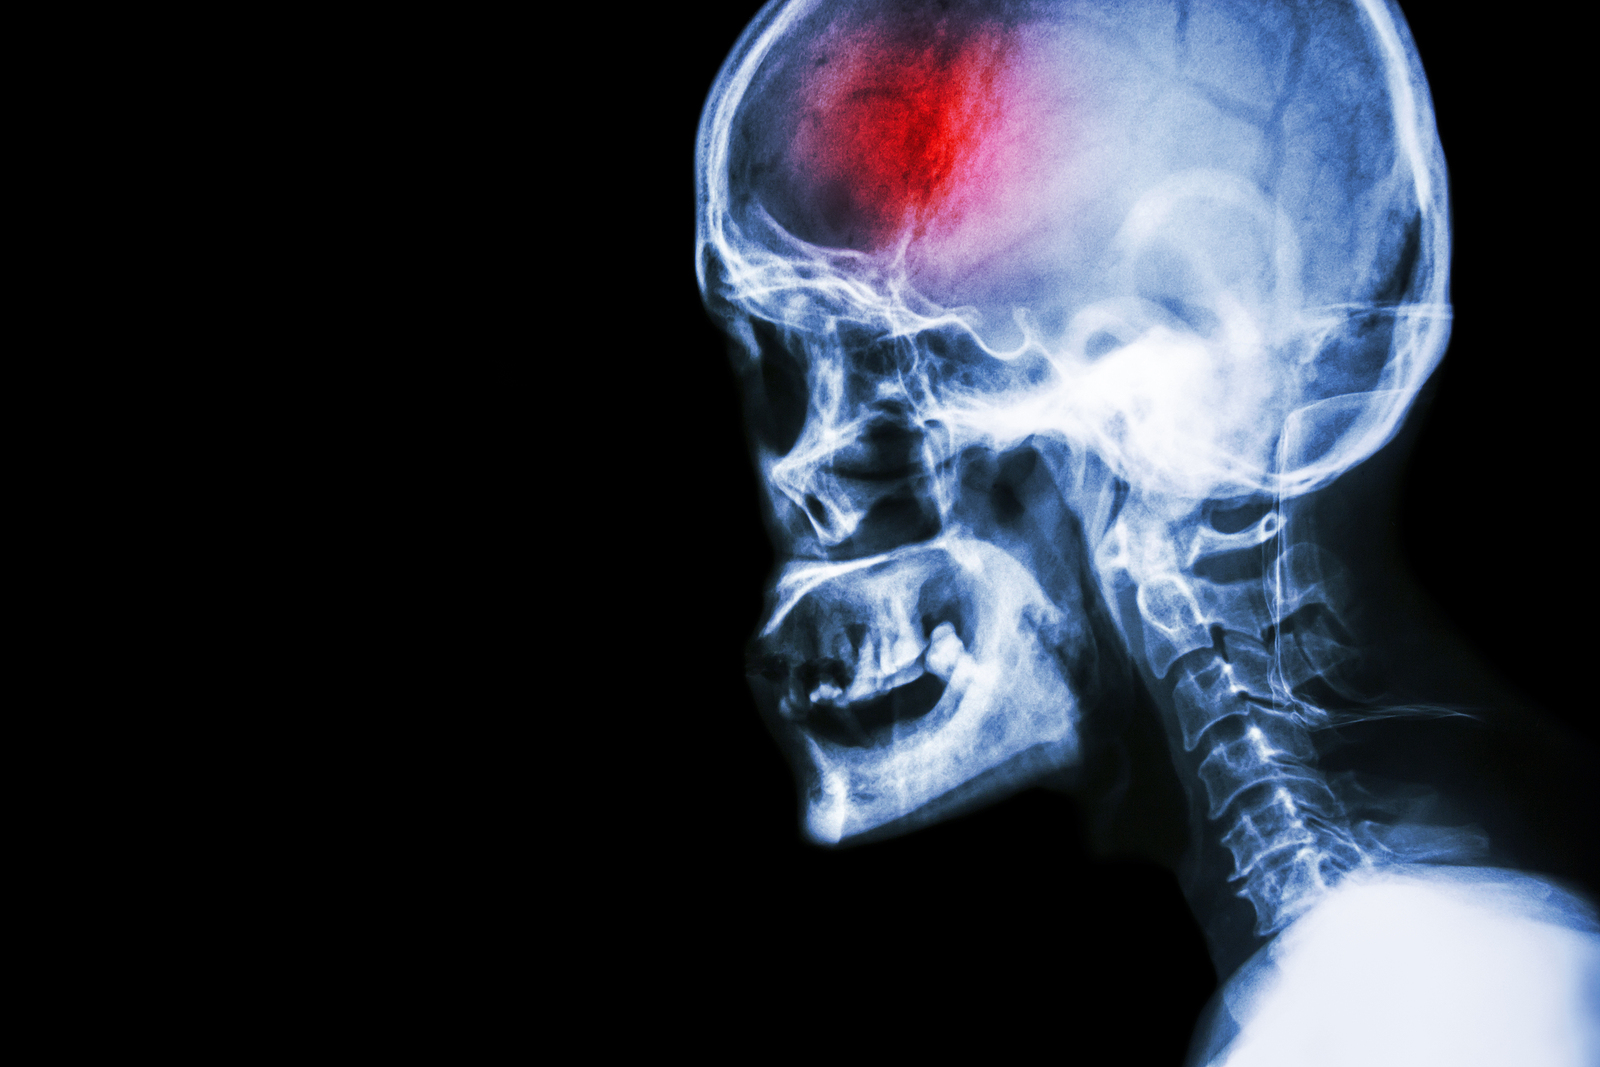

A stroke (previously known as a cerebrovascular accident) when there is a decreased flow of blood to the brain from either a blockage in the blood vessels that supply the brain (ischemic stroke), or a bleed from the blood vessels that supply the brain (hemorrhagic stroke). When the blood flow to the brain is blocked it prevents the brain from getting the needed oxygen and nutrients to function. Without oxygen the brain cells can be permanently damaged or die and the physical and mental functions related to that area of the brain will be affected. A stroke is a medical emergency and rapid treatment is crucial to decreasing the damage caused by a stroke.

• Ischemic stroke: a stroke that is caused by a blockage (clot) that disturbs the blood flow to the brain.

• Hemorrhagic stroke: a stroke that is caused by a bleed that disturbs the blood flow to the brain and puts pressure on the surrounding tissue.

Computed Tomography (CT) scan and/or Magnetic Resonance Imaging (MRI) scan: These tests are done on your brain and used to locate the exact location of the stroke and to determine if it has been caused by a blockage or a bleed. These tests can also help rule out other conditions that may be causing symptoms, such as an infection or a brain tumour